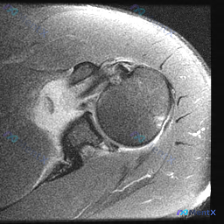

整理到一份肩关节影像病例资料,先放单张轴位T2加权MRI: > 影像基础:肩关节轴位T2加权序列,可见肱骨头、关节盂、肩胛下肌等结构,前下盂唇区域存在局灶性高信号影,肱骨头骨皮质完整,无明显关节积液或巨大占位。 想问问大家,仅根据这张图像的表现,第一反应会先往哪个方向考虑?有没有需要特别注意的鉴别点...

看到一个肩关节病例,临床怀疑盂唇病变,但只提供了一张轴位T2加权MRI图像。先看影像分析结果: 轴位MRI表现: - 前、后盂唇形态基本完整,信号均匀,未见明确撕裂信号 - 肩胛下肌腱、冈下肌腱、肱二头肌长头腱信号正常,未见撕裂 - 肱骨头与关节盂对位良好,骨质及软组织未见明显异常 核心矛盾:临床怀...